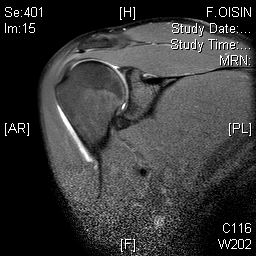

The normal shoulder has several layers.These layers mean that the shoulder joint is several centimeters below the skin. Swelling in the shoulder is not easily seen unless it is very severe.

Deep to the deltoid run muscles from the shoulder blade attaching to the top of the humerus just at the edge of the joint. These muscles are known as the rotator cuff. They form a near continuous attachment to the bone so an injury to the tendon (the white sinewy part of the muscle that attaches to the bone) of one muscle often extends into its neighbouring rotator cuff muscle.

Deep to the rotator cuff lies the deepest layer of soft tissue, the joint capsule. The capsule is a thin but strong fibrous layer that is supple enough to allow full movement but strong enough to stop the shoulder dislocating. It is inflammation in the joint capsule which causes the capsule to stiffen reducing movement causing the symptoms of a frozen shoulder. At the opposite extreme tearing of the capsular attachment to bone is what allows shoulders to dislocate.

Beneath all these layers lie the cartilage covered bones of the shoulder joint formed by the humeral head (top of the humerus) and the glenoid (the oval joint surface of the scapula). Arthritis in the bones of the shoulder joint results in loss of the white shiny and smooth articular cartilage leaving the much rougher bones directly in contact with each other.